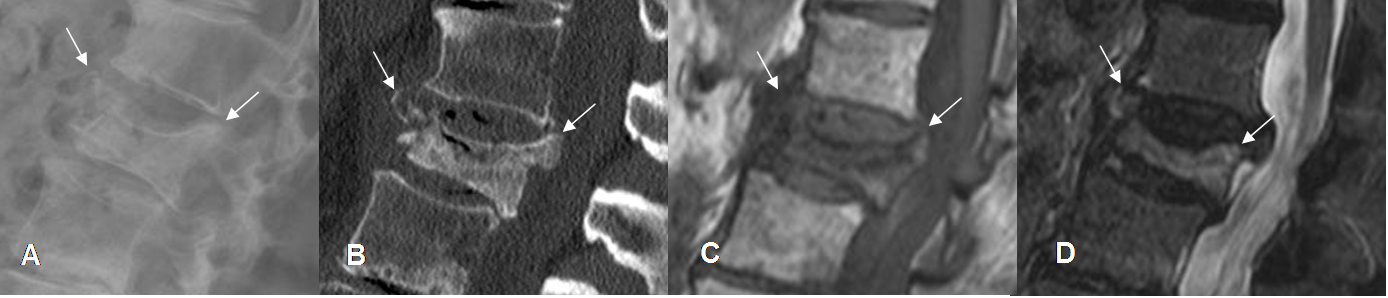

Fig 225. Enfermedad metastásica.

A: RM sagital en T1, B: RM sagital en T2, C: RM sagital en STIR y D: RM sagital en difusión.

Pérdida de altura en el cuerpo de L4, hipointenso en T1 y T2 e hiperintenso en STIR, con borde posterior convexo que comprime el saco dural. La lesión es hiperintensa en la difusión, lo que indica origen tumoral, por metástasis de pulmón.